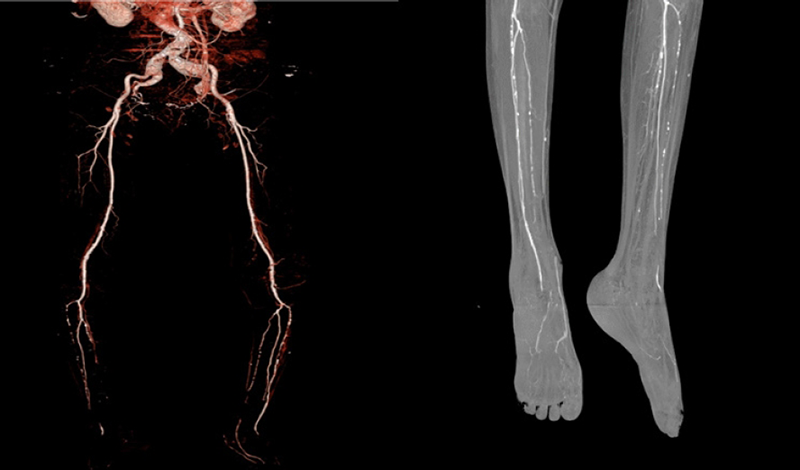

انواع روشهای آنژیوگرافی

| نوع آنژیوگرافی | روش انجام | کاربرد اصلی | ملاحظات |

|---|---|---|---|

| آنژیوگرافی دیجیتال تفریقی (DSA) | تزریق ماده حاجب از طریق کاتتر | تصویربرداری دقیق از عروق و انجام مداخلات درمانی | تهاجمی، نیاز به بستری، دقت بالا |

| CT آنژیوگرافی | تزریق ماده حاجب و اسکن CT | نقشهبرداری از عروق بزرگ و متوسط | غیرتهاجمی، تصاویر سهبعدی |

| MR آنژیوگرافی | تصویربرداری با یا بدون ماده حاجب | بررسی عروق بدون اشعه یونیزان | مناسب برای بیماران با نارسایی کلیه |

| آنژیوگرافی با CO2 | استفاده از گاز CO2 به جای ماده حاجب | مناسب برای بیماران با حساسیت به ماده حاجب | کمخطر، بدون عوارض کلیوی |

| آنژیوگرافی داپلر | استفاده از امواج صوتی | بررسی جریان خون و سرعت آن | غیرتهاجمی، قابل تکرار |